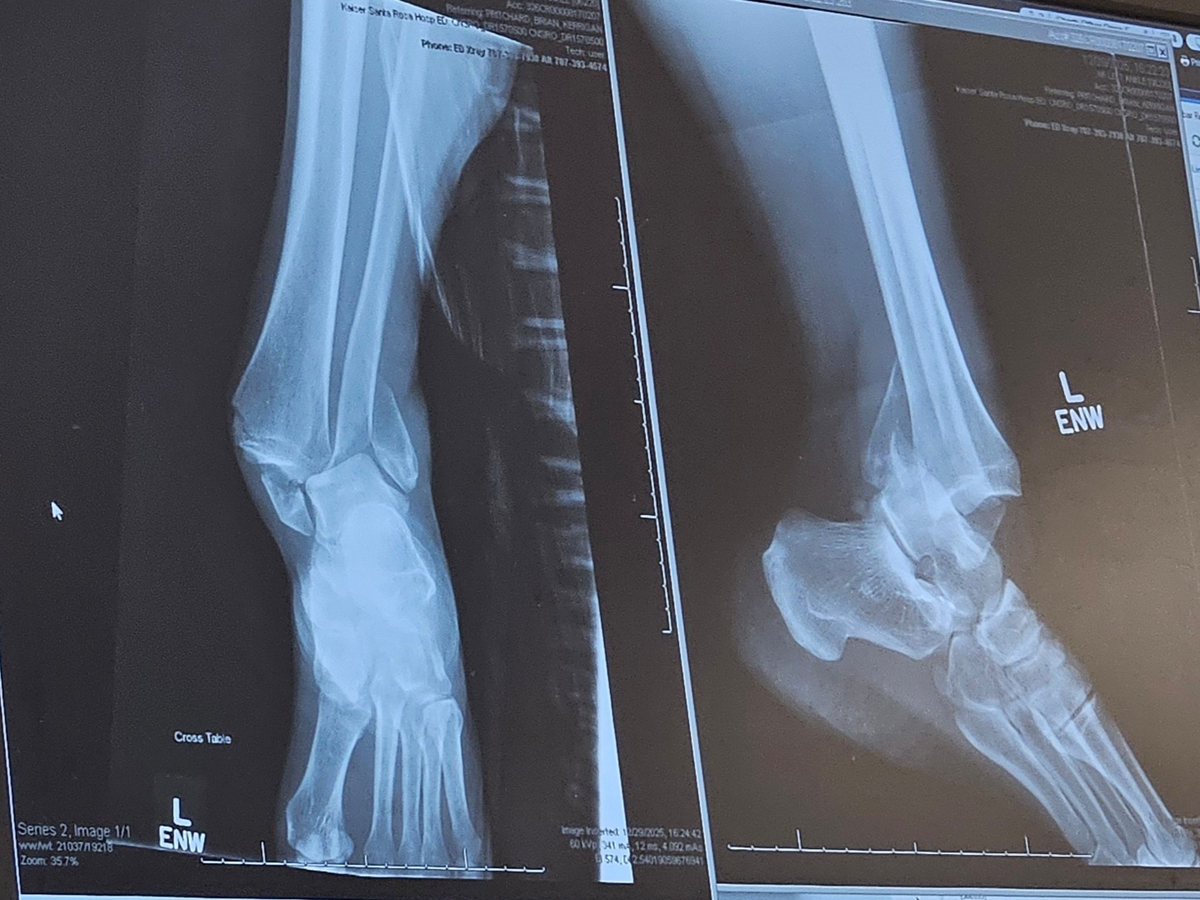

Over Christmas break, my kids and I took a short family adventure to San Francisco—grateful for time together, laughter, and making memories. Just a few days later, on Monday, December 29th, while roller skating with family at our local rink, I experienced a sudden and freak accident that resulted in a severe ankle injury.

I stayed calm, and thankfully my family was there to help care for the kids while paramedics transported me by ambulance to the hospital. I spent the day in the ER, where I was placed in a soft cast and sent home with pain medication while awaiting surgery.

Surgery took place on January 2nd. Since then, recovery has been more challenging than expected. I am currently non-weight-bearing on my left ankle and must remain mostly flat with my leg elevated while my body heals. Pain management has been difficult, and day-to-day tasks require support.